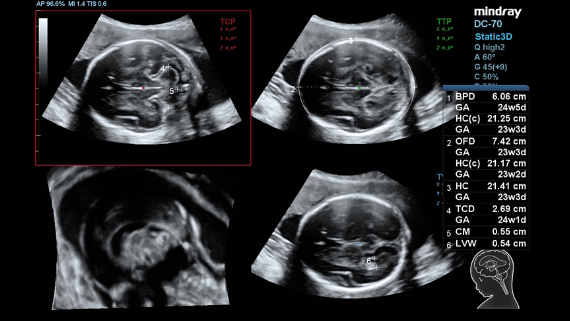

DC-70 Exp

–°–Њ–≤–Љ–µ—Б—В–љ–Њ —Б —Б–Њ–≤—А–µ–Љ–µ–љ–љ—Л–Љ–Є —Г–ї—М—В—А–∞–Ј–≤—Г–Ї–Њ–≤—Л–Љ–Є —В–µ—Е–љ–Њ–ї–Њ–≥–Є—П–Љ–Є –љ–Њ–≤–Њ–µ —А–µ—И–µ–љ–Є–µ –Њ—В Mindray –њ—А–µ–Њ–±—А–∞–Ј—Г–µ—В –∞–Ї—В—Г–∞–ї—М–љ—Л–µ –Ј–∞–і–∞—З–Є –Ї–ї–Є–µ–љ—В–Њ–≤ –≤ –Ї–ї–Є–љ–Є—З–µ—Б–Ї–Є–µ –њ–Њ—В—А–µ–±–љ–Њ—Б—В–Є.

–°–Є—Б—В–µ–Љ–∞ DC-70 Exp —Б X-Insight –њ–Њ–Љ–Њ–≥–∞–µ—В —Г–њ—А–∞–≤–ї—П—В—М –њ–Њ–≤—Б–µ–і–љ–µ–≤–љ–Њ–є –Ї–ї–Є–љ–Є—З–µ—Б–Ї–Њ–є –њ—А–∞–Ї—В–Є–Ї–Њ–є —Б –ї–µ–≥–Ї–Њ—Б—В—М—О –Є —Г–≤–µ—А–µ–љ–љ–Њ—Б—В—М—О.

–Ю—Б–љ–Њ–≤—Л–≤–∞—П—Б—М –љ–∞ –≥–ї—Г–±–Њ–Ї–Њ–Љ –њ–Њ–љ–Є–Љ–∞–љ–Є–Є –њ–Њ—В—А–µ–±–љ–Њ—Б—В–µ–є –Ї–ї–Є–µ–љ—В–Њ–≤, –Ї–Њ–Љ–њ–∞–љ–Є—П Mindray —А–∞–Ј—А–∞–±–Њ—В–∞–ї–∞ —Б–Є—Б—В–µ–Љ—Г DC-70 Exp —Б X-Insight, —З—В–Њ–±—Л –Њ–±–µ—Б–њ–µ—З–Є—В—М eXpress Clarity, eXceptional Intelligence, eXceeding Experience.